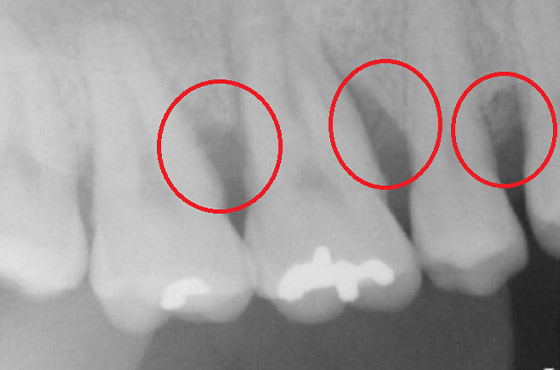

歯周病が進行して、歯の根元まで炎症が広がることがあります。右の写真をご覧ください。赤丸で囲んだ分が黒くなっています。ここは、歯肉が衰え、歯と歯肉の間にできたすき間です。ここに付着した歯石を取り除くことはできません。放置すると歯周病がさらに進行して、やがて抜歯となってしまうでしょう。